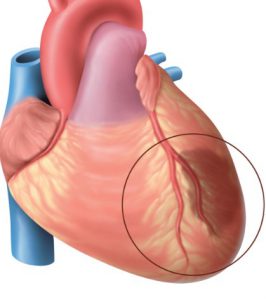

- Érelmeszesedés és magas vérnyomás jelennek meg a fő kockázati tényezők fejlesztésére kóros állapotok a szív, mely a fő célszerv. Thrombosis erek etetés a szív határozza meg a fejlesztési iszkémiás szívizom, amely magában foglalja a halál egy szívroham.

Az atheroscleroticus erek szűkülete nem befolyásolhatja az a szív állapota. A magas vérnyomás növeli a növekedés és a preload a fő izmos test. Az együttes hatása Ezen patológiás a gyengült szív ad kifejezett szívelégtelenség tünetei, ami azt jelenti, extra kezelést.

Ateroszklerózis és a magas vérnyomás ritkán alakul elszigetelten és gyakran együtt patológia.

- Az okok a szívbetegségek és hozzon létre a komplex diagnosztikai eljárások. Az angiográfia hajók teljesebb képet felfedi vérellátását szervek, amelyek tapasztal egy enzim vagy bármely más funkcionális károsodást.